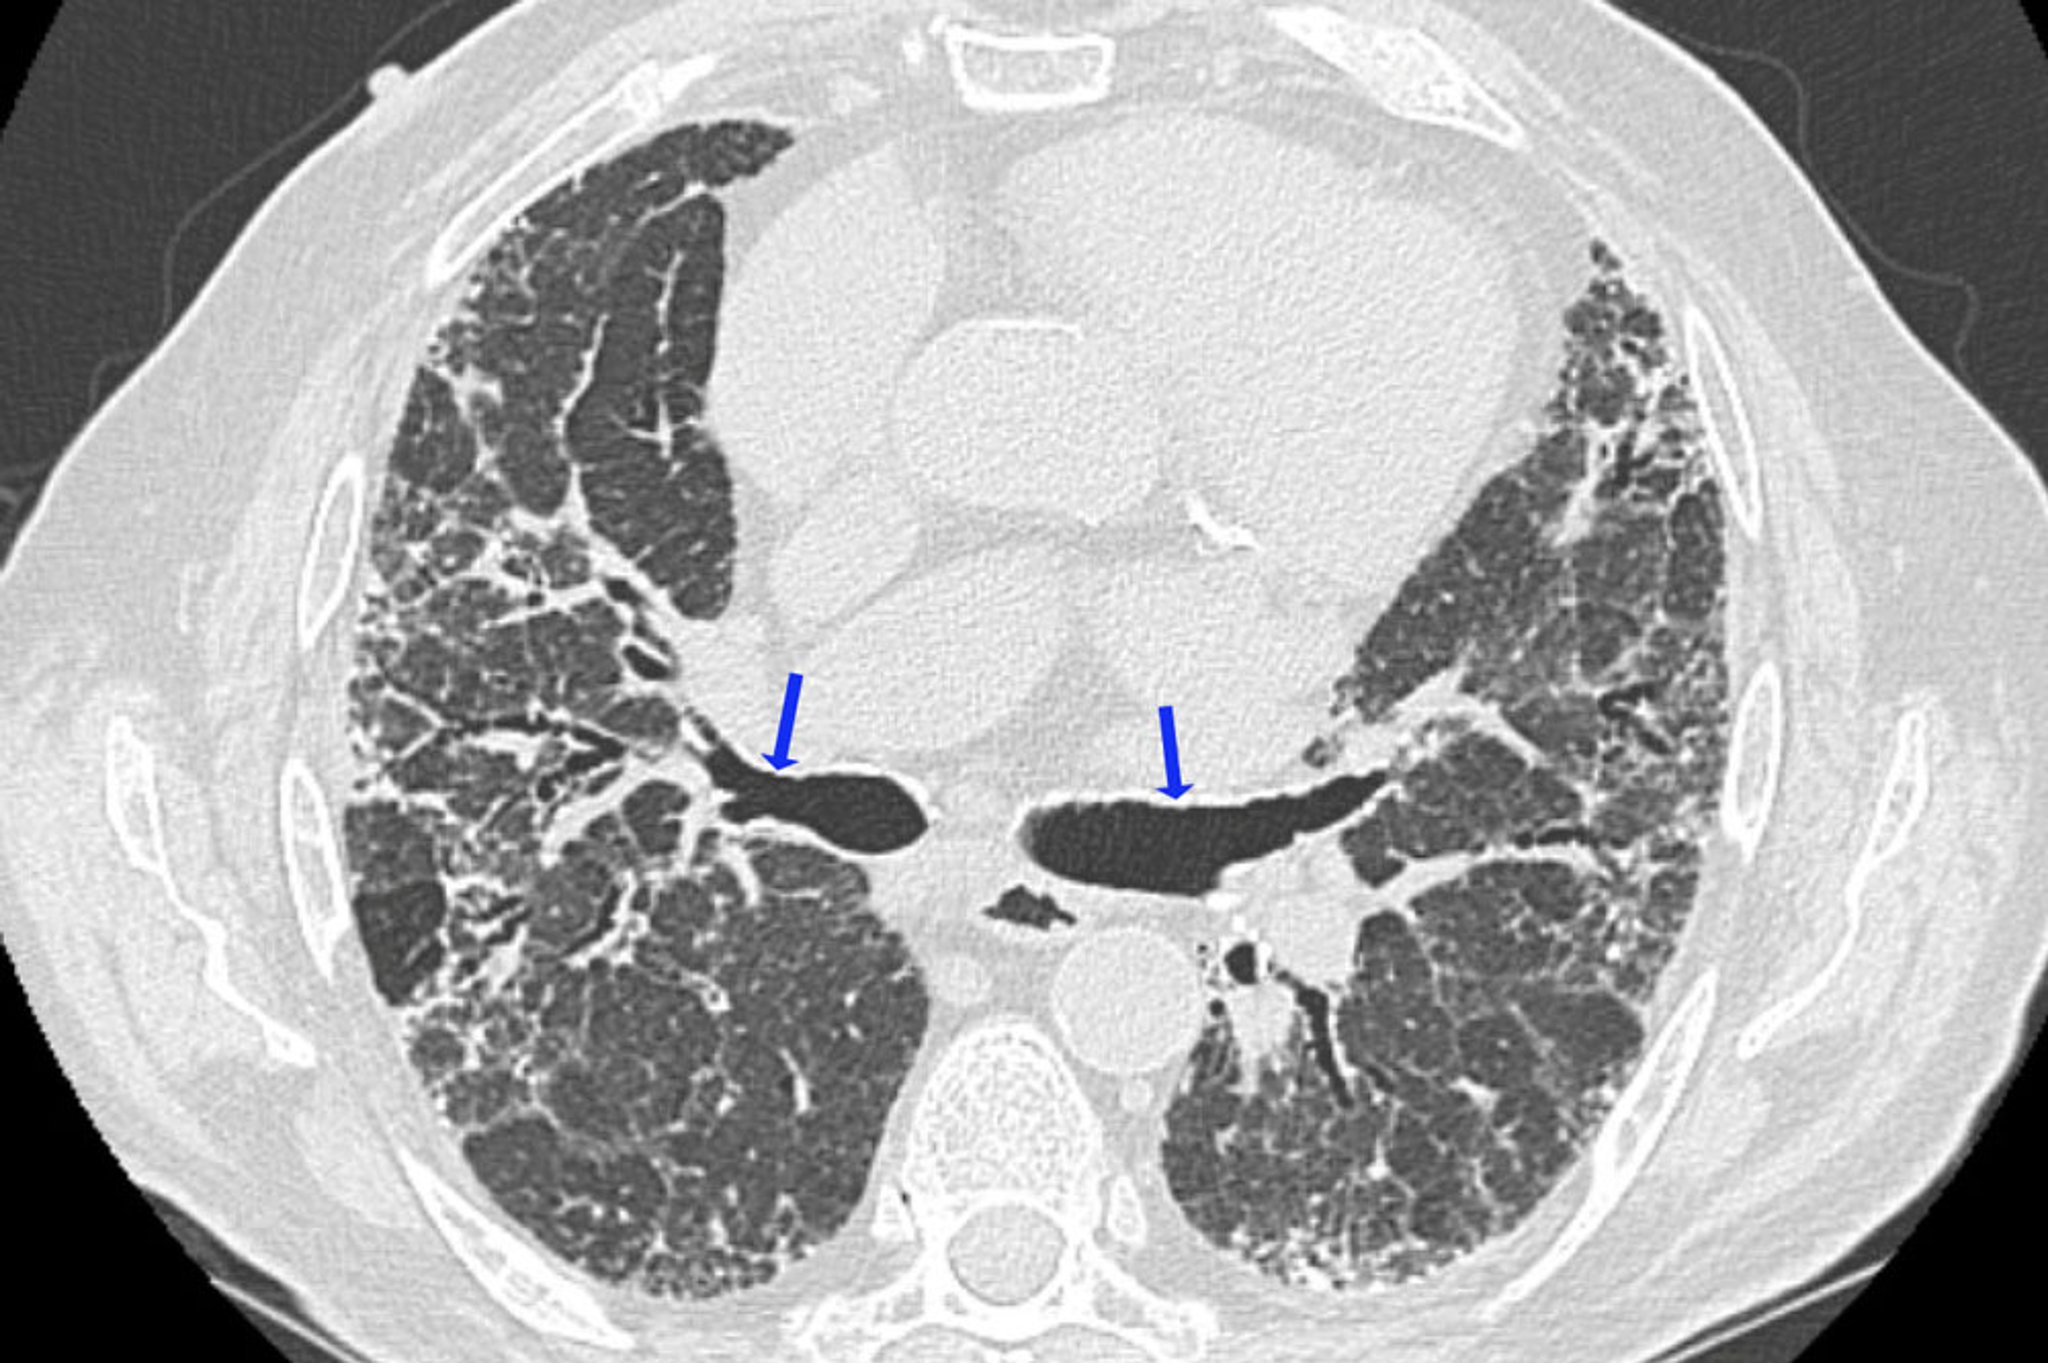

Viêm phổi kẽ quá mẫn mạn tính

Chụp CT độ phân giải cao này cho thấy các dấu hiệu xơ hóa, bao gồm hình mắt lưới không đều và giãn phế quản do co kéo (mũi tên). Các vùng có mật độ phổi giảm tương thích với các vùng tắc nghẽn đường thở. Kết hợp các dấu hiệu này gợi ý đến viêm phổi kẽ do quá mẫn.

Hình ảnh do bác sĩ Joyce Lee cung cấp